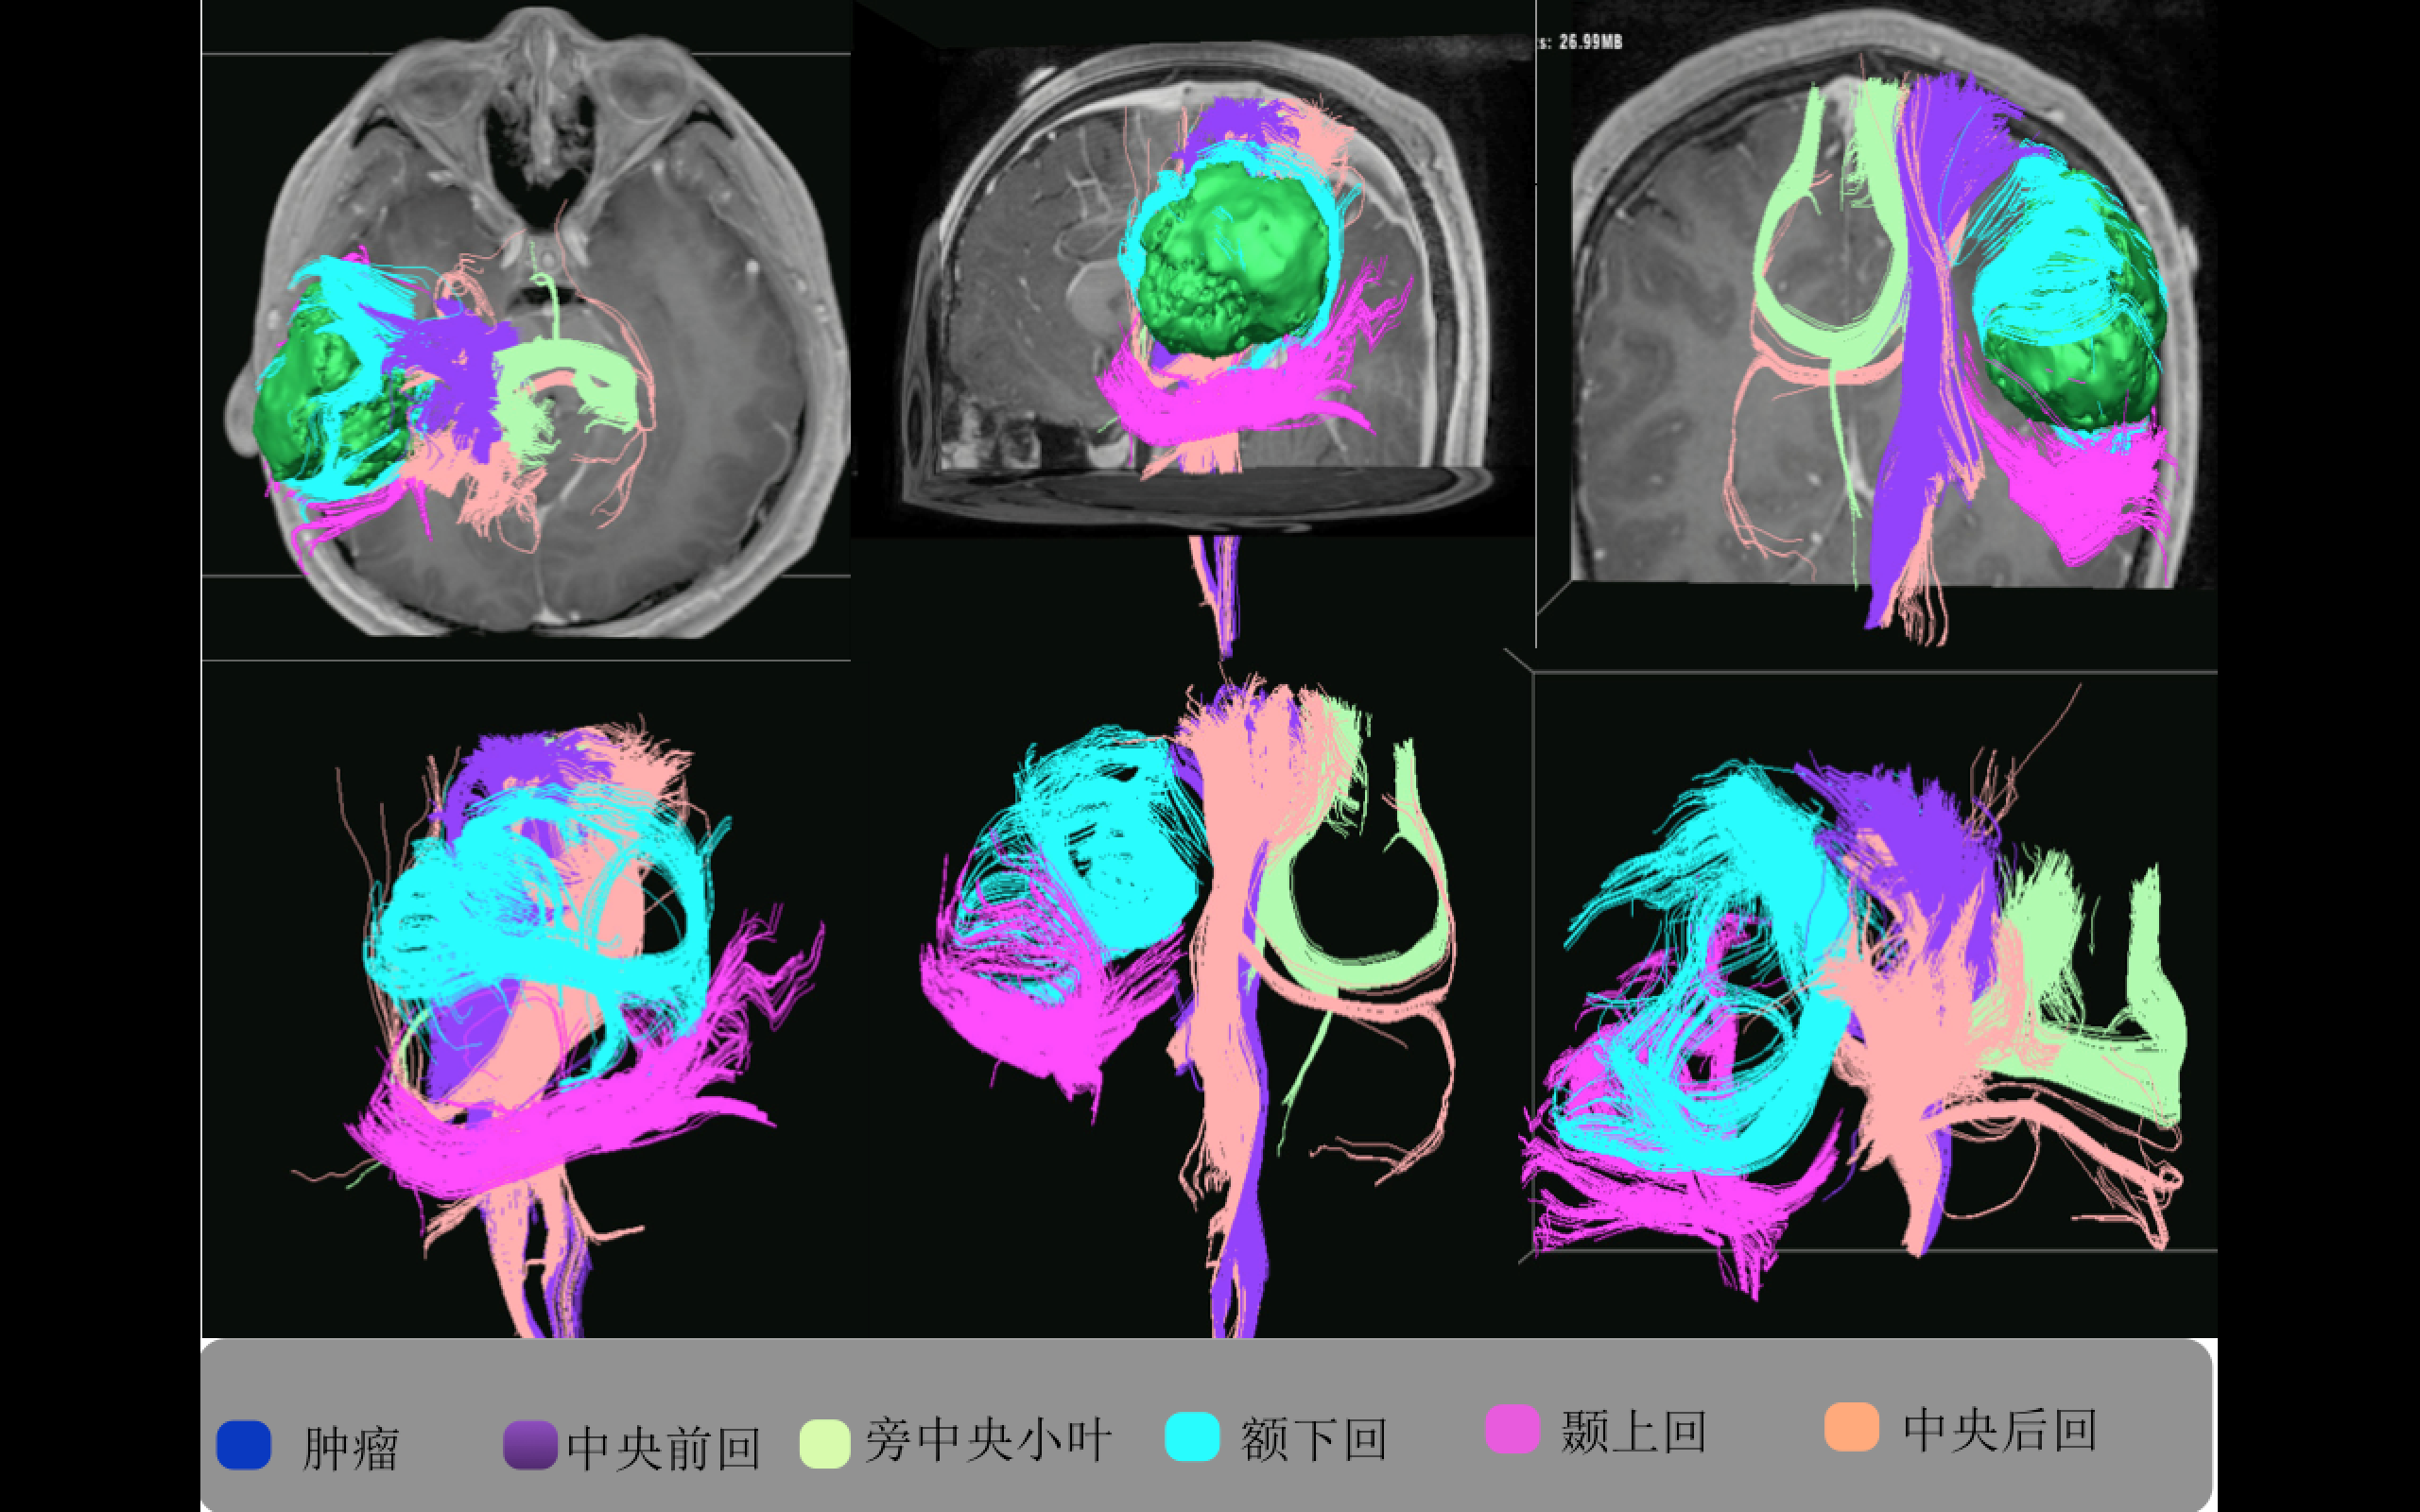

多模态影像融合助力精准切除功能区胶质瘤

多模态影像融合及术中导航技术精准切除功能区胶质瘤